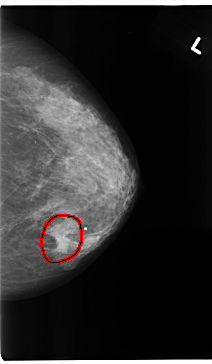

C_0175_1.LEFT_MLO

LEFT_MLO LINES 4752 PIXELS_PER_LINE 2472 BITS_PER_PIXEL 12 RESOLUTION 50 OVERLAY

FILE: C_0175_1.LEFT_MLO.OVERLAY

TOTAL_ABNORMALITIES 1

ABNORMALITY 1

LESION_TYPE MASS SHAPE ROUND MARGINS SPICULATED

ASSESSMENT 5

SUBTLETY 5

PATHOLOGY MALIGNANT

TOTAL_OUTLINES 1

BOUNDARY